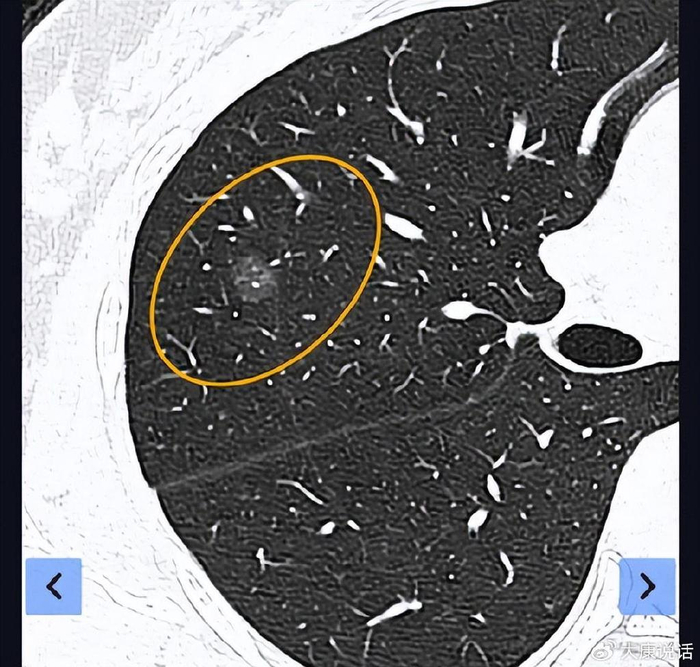

双肺多发磨玻璃结节怎么办先期一网打尽左肺5个腺癌